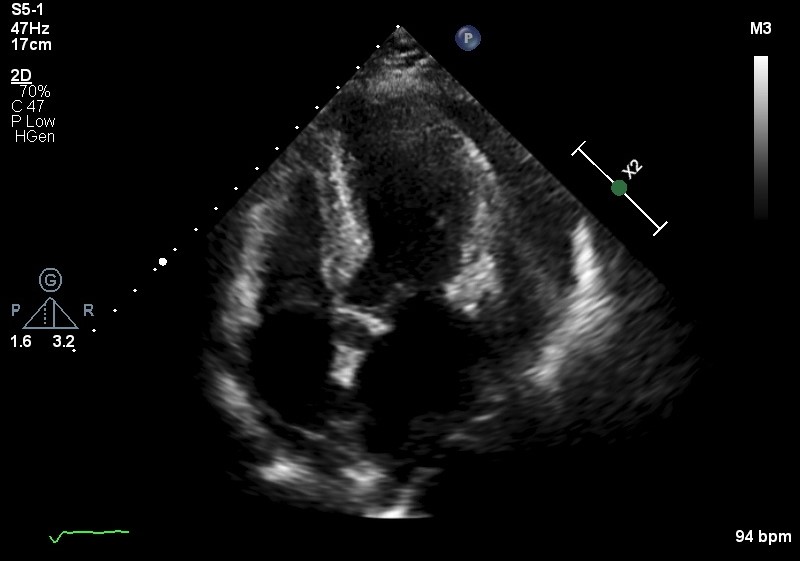

ECG showed sinus rhythm, RBBB with small QRS complexes. Her laboratory workup including full blood count and metabolic panel was unremarkable with Troponin recorded at 13pg/ml. Chest XRay showed cardiomegaly. Urgent echocardiogram showed ejection fraction of 45% with global pericardial effusion with right ventricular collapse during diastole. Emergency pericardial tapping was done with 480cc serous fluid drained, repeated echocardiogram showed near total resolved pericardial effusion.